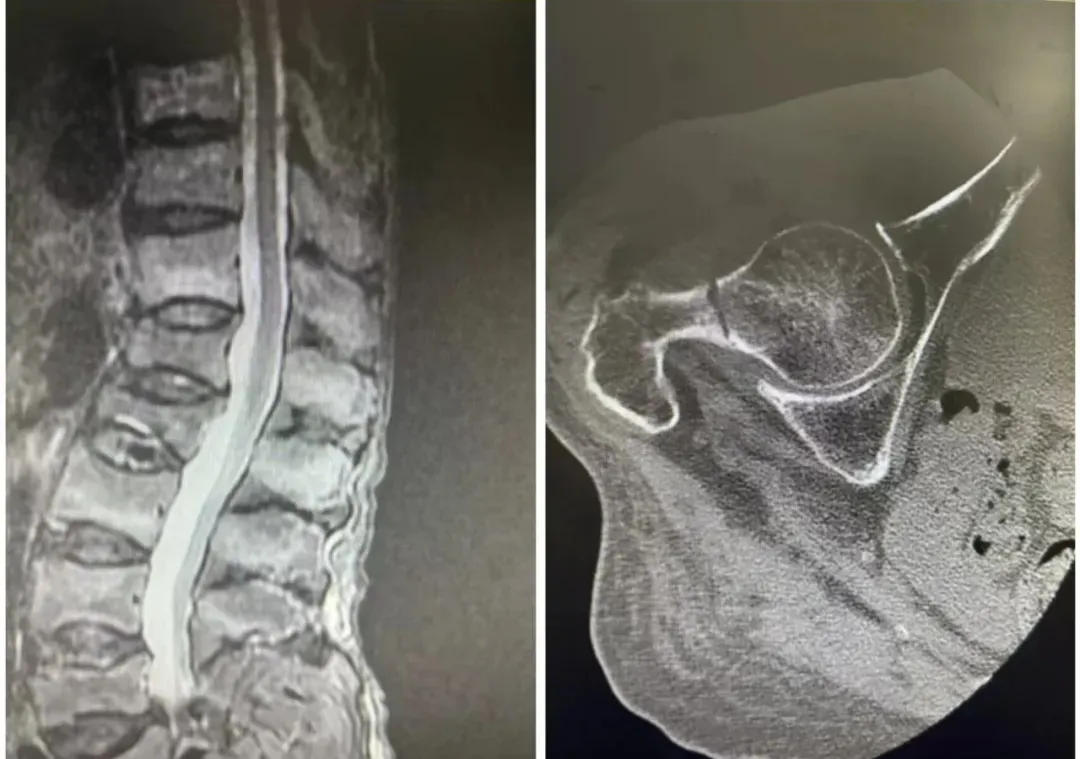

1個(gè)月前,74歲的患者在家中坐凳時(shí)不慎摔倒,當(dāng)即出現(xiàn)右髖部、腰背部劇烈疼痛,伴隨肢體活動(dòng)受限。受傷后患者自行臥床休息,癥狀始終未緩解,遂在家屬陪同下來渭北中心醫(yī)院就診。DR影像學(xué)檢查提示,患者存在右側(cè)股骨頸骨折,胸9、10、11椎體骨折,腰2、3椎體骨折,同時(shí)合并腰5椎體椎弓峽部裂、脊柱后凸畸形,門診隨即以 “右股骨頸骨折” 將患者收住入院。

在與患者及家屬充分溝通、完善術(shù)前準(zhǔn)備后,骨一科(關(guān)節(jié)骨科)團(tuán)隊(duì)在局麻下為患者實(shí)施經(jīng)皮椎體成形術(shù)。該微創(chuàng)術(shù)式創(chuàng)傷小、止痛效果確切,可快速緩解脊柱骨折引發(fā)的疼痛,為患者早期活動(dòng)創(chuàng)造條件。不久后,團(tuán)隊(duì)再次為患者在全麻下實(shí)施右側(cè)股骨頸骨折FNS內(nèi)固定術(shù),術(shù)中操作精準(zhǔn),患者生命體征平穩(wěn),手術(shù)順利完成。術(shù)后,骨一科(關(guān)節(jié)骨科)團(tuán)隊(duì)為患者制定精細(xì)化康復(fù)管理方案,規(guī)范開展對(duì)癥治療與康復(fù)指導(dǎo)。在醫(yī)護(hù)人員精心照護(hù)下,患者恢復(fù)順利,疼痛完全緩解,肢體活動(dòng)功能逐步恢復(fù),無術(shù)后并發(fā)癥發(fā)生,現(xiàn)已痊愈出院。